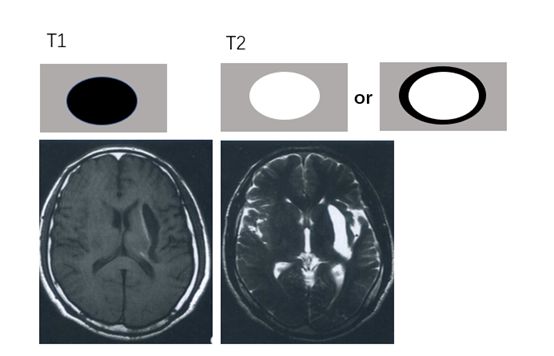

▎超急性期:<6小时至<24小时

血液刚从动脉里流出来,红细胞是完整的,内含氧合血红蛋白,最“原汁原味“。超急性期尚未凝固的血液表现出血液在磁共振检查中长T1长T2特性,即T1WI上表现为略低信号,在T2WI上呈现高信号。超急性期3小时后可出现血肿周围水肿。